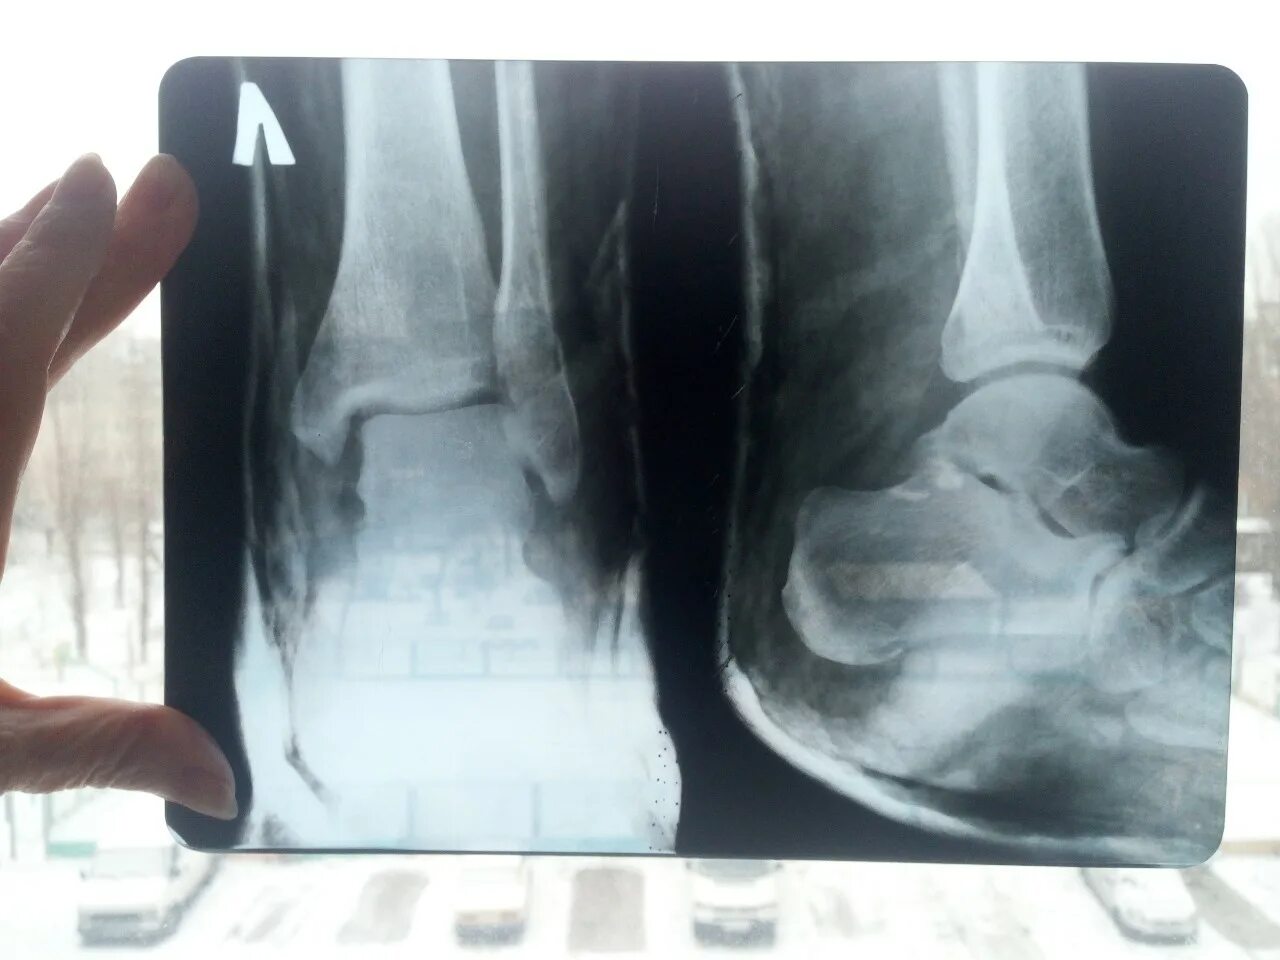

Вывих со смещением